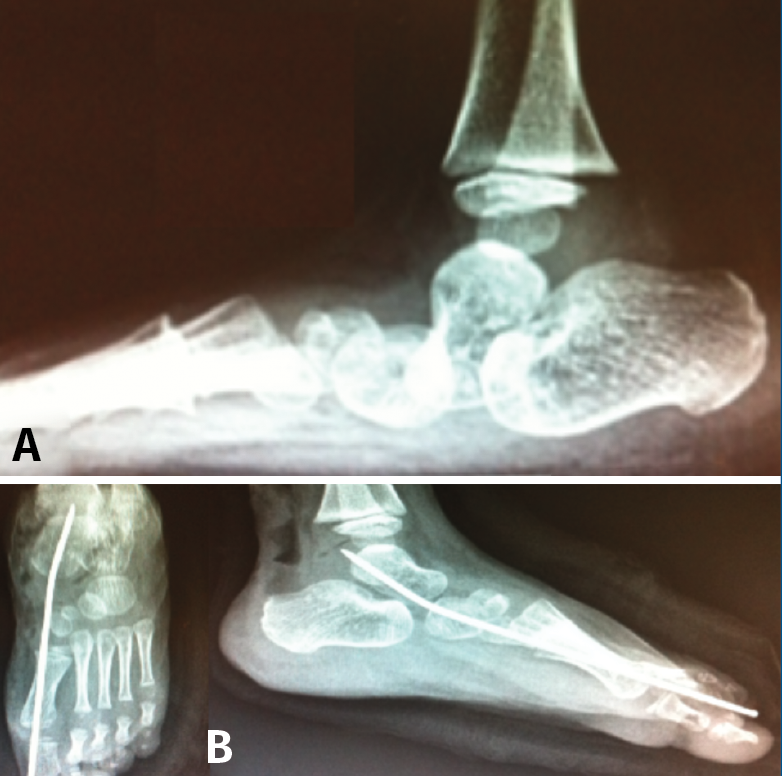

Pie en serpentina (skewfoot)

El pie en serpentina o en Z constituye una deformidad rara en el pie, que combina valgo del retropié con aducción del antepié (Figura 18).

Figura 18. Pies en serpentina. A: radiografía dorsoplantar de la deformidad en serpentina; B: imágenes radiológicas postoperatorias inmediatas, donde se aprecia osteotomía de Mosca y técnica de Cahuzac percutánea; C y D: imagen clínica y radiológica un año tras la intervención.

A menudo infradiagnosticado, suele presentarse como un metatarso aducto resistente al tratamiento. En la radiografía se manifiesta con signos de valgo del retropié con divergencia AC aumentada y aducción del antepié al nivel de la articulación de Lisfranc.

En caso de indicación quirúrgica se debe corregir el doble componente de la Z con osteotomía de alargamiento de la columna externa (para corregir el valgo) más corrección del antepié mediante técnica de Cahuzac (apertura de la cápsula C1M y osteotomía de los metatarsianos centrales) modificada en percutánea(20).